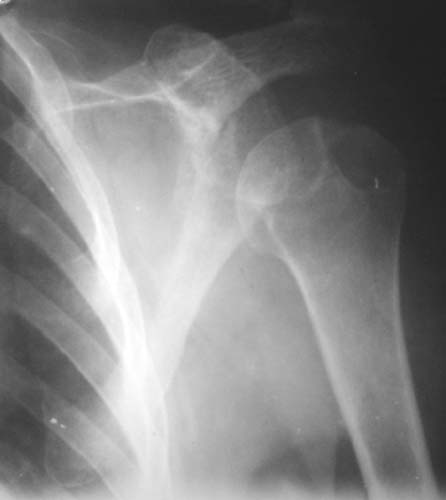

r1r2r3

Уважаемые коллеги!Женщина, 60 лет. 3 недели назад упала с упором на отведенную левую руку. Почувствовала боль в левом плечевом суставе. За помощью не обращалась. 2 недели "мази и припарки". Затем - рентгенограмма (r1 и r2), жалобы на боли,ограничение движений...

Активное отведение 80 гр., при пальпации - головка плечевой кости безболезненно вправляется и тут же самостоятельно вывихивается. Наложена косыночная иммобилизация, рентгенография (r3) и МРТ.В нашем диагностическом центре МРТ исследование плечевого сустава выполнено впервые, опыта у нас маловато :(.Вопросы: уточнение диагноза? какие исследования провести? тактика лечения?

Как Вам известно, в некоторых случаях вывихи плеча сопровождаются разрывом ротаторной манжетки, отрывному перелому большого бугорка что приводит к потере наружной ротации и отведения плеча. На представленных рентгенограммах перелом не виден.

МРТ должен показать разрыв манжетки, но признаться я не большой эксперт по чтению МРТ сканов, хотя затемнение, отек мягких тканей по задней поверхности плеча видны Обычные рентгенограммы демонстрируют остеолизис в области большого бугорка.

1. На рентгене - нижний подвывих плеча и очаг остеолиза суставного бугорка с четкими контурами (вдавленный перелом на фоне остеопороза ? доброкачественная опухоль? аваскулярный некроз ? (хотя ни разу не слышал об аваскулярном некрозе плеча..)

Судя по снимкам, речь идTт о типичном случае Hill-Sachs Lesion. По этому поводу я позволю себе некоторый экскурс:

97 % всех вывихов плеча происходит по механизму комбинации отведения, разгибания и наружной ротации (А. Гринспан). В момент вывиха головка плеча ударяет о нижний край гленоида, что ведет к вдавленному или компрессионному перелому одной или обеих структур. Чаще всего, однако, повреждение возникает в задней латеральной области головки плечевой кости на переходе от головки к шейке. Этот диагноз можно выставить на основании рентгеновского снимка в переднезадней проекции с внутренней ротацией плеча. Несколько реже видно повреждение гленоида о передненижний перелом края. То, что мы называем Bankart Lesion. Это повреждение видно на ре. снимке в п.з. проекции при нейтральной позиции плеча. Разумеется хрящевые и мягкотканные повреждения (в смысле Банкарт) мы увидим лучше всего на ЯМР.